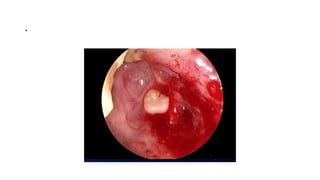

Bulbar Transconjuctival Orbitotomy

• .

Bulbar conjunctival incision

Bulbar transconjuctival incision

Cavernous Hemangioma